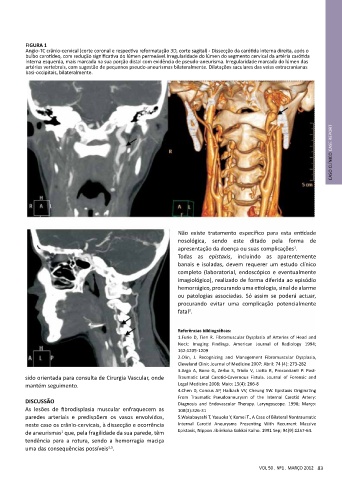

FIGURA 1

Angio-TC crânio-cervical (corte coronal e respectiva reformatação 3D, corte sagital) - Dissecção da carótida interna direita, após o

bulbo carotídeo, com redução significativa do lúmen permeável.Irregularidade do lúmen do segmento cervical da artéria carótida

interna esquerda, mais marcada na sua porção distal com evidência de pseudo-aneurisma. Irregularidade marcada do lúmen das

artérias vertebrais, com sugestão de pequenos pseudo-aneurismas bilateralmente. Dilatações saculares das veias extracranianas

basi-occipitais, bilateralmente.